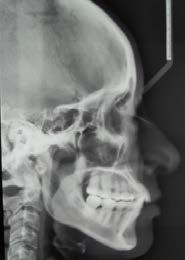

En la radiografía lateral de cráneo se ve el diagnósitico: clase II esqueléti ca, con crecimiento hiperdivergente, mordida profunda anterior (Figura 4).

Estudios radiográficos de inicio en la radiografía lateral de cráneo (Figu ra 5) tenemos la clase II esquelética con un ANB de 7°, hiperdivergencia, aumento de la altura facial anterior, disminución de la altura facial poste rior y proclinación del incisivo supe rior con 1 a plano palatino de 121° e incisivo inferior de 1 a plano mandi bular de 99°.